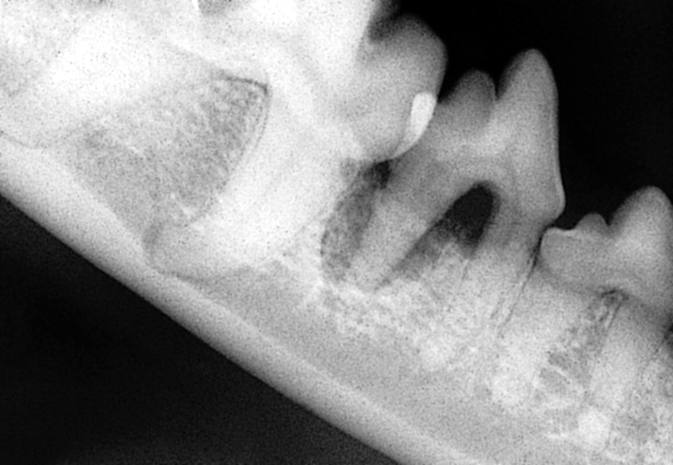

Radiograph showing more than 50% attachment loss of mesial root

Attachment loss is now greater than 50%. If disease is generalised, horizontal bone loss is most likely, whereas localised lesions, such as the palatal aspect of the maxillary canines, may present infrabony pockets with vertical bone loss.

Severe/total attachment loss of mesial root 408